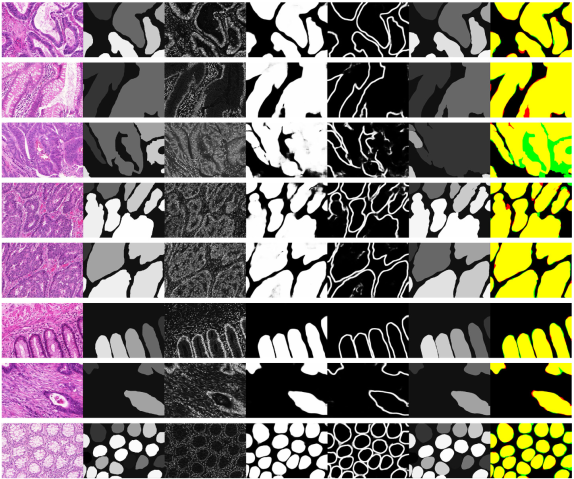

Caractérisation de biomarqueurs histologiques basée sur l'analyse d'images numérisées de lames histologiques entières et utilisant des méthodes d'apprentissage (dont l'apprentissage profond) et de recalage d'images combinant plusieurs marqueurs immunohistochimiques.